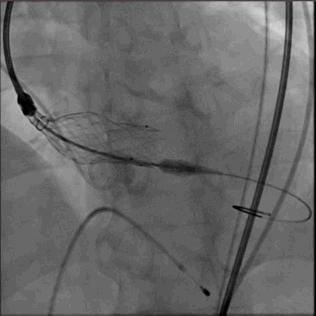

瓣膜释放

VenusA 26支架,高位 释放

1.ring释放到mark点往下2mm处,造影观察位置(此时仍可以调整位置)

2.瓣膜释放瓣架打开 瓣架开始附着在钙化区 高速起搏 血压下降 系统保持相对稳定

3.支架开始贴壁,血压开始恢复,支架下部锚定区固定,停止起搏 。

4.造影观察冠脉情况 瓣叶运动工作 是否PVL 返流等